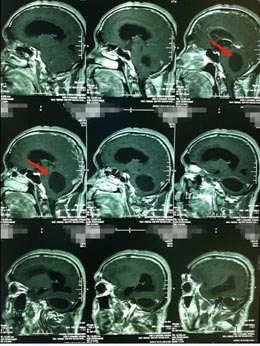

“门外一男一女吃力的扶着一个一米八的中年男子慢慢地跛行进来,我已经猜测到有八九分了:右侧小脑半球占位并梗阻性脑积水,小脑扁桃体下疝”,接诊的医院副院长、神经外五科的鲁明说。张先生的脑部影像检查也证实了鲁明的诊断:

由于肿瘤引起的继发性小脑扁桃体下疝,向下进入颈椎的椎管内,导致颈椎椎管狭窄,妨碍脑脊液循环形成脑积水。从治疗的角度,外科手术是必然的选择,目的是切除肿瘤后解除枕骨大孔和上颈椎对小脑、脑干脊髓、第四脑室及该区其他神经结构的压迫,在可能的范围内分离枕大池正中孔和上颈髓的蛛网膜粘连,解除神经症状,缓解脑积水。